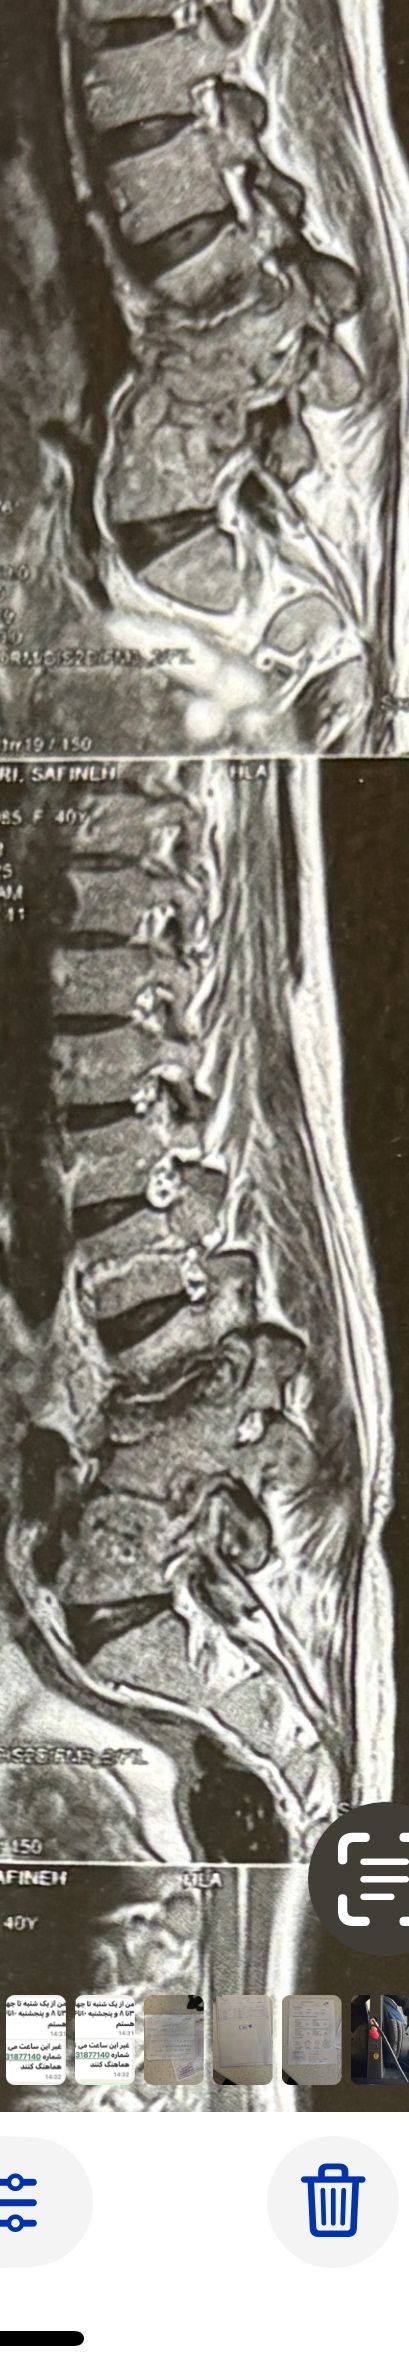

46 years old female patient presented to my clinic yesterday june 1/2025 with LBP and radicular L leg pain for several months which hasn’t responded to physio 2 neurosurgeons have visited her and didn’t suggest any surgery Neurological exam was unremarkable please see her mri/ emg/ncv and her huge tarlov cyst and possible L IVF L4-5 hyperbulge I ordered sacrum mri and ct scan and new emg/ncv and asked her with her sacral Ct scan and MRI first sees another two famous neurosurgeons and see if that large cyst is the reason for her pain if not i can work on her L4-S1 area Do you think her radicular pain can originate from her large cyst in sacrum? Do you consider surgery and removing her sacral cyst?